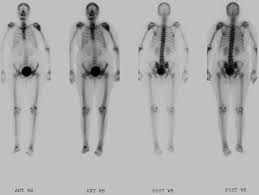

Medullary Thyroid Cancer In Children And Teens Together from stjude.scene7.com Signs and symptoms of thyroid cancer (american cancer society) also in spanish. Both occur particularly with liver metastasis, and either symptom may be the first manifestation of the disease. But as it grows, it can cause pain and swelling in your neck. Treatment strategies and predicting lymph node metastasis in elderly patients with. Your doctor may recommend periodic blood tests or thyroid scans to check for signs of a thyroid cancer. Symptoms of thyroid cancer, the acs reports, can include: The uzi signs of thyroid cancer are conducted in order to detect this disease. So, for today it is the most simple and accessible method.

Aggressive Features In Some Small Thyroid Tumors Increase The Risk For Metastasis Eurekalert Science News from www.eurekalert.org View the most common signs and symptoms of thyroid cancer that you need to know about. Thyroid cancer can cause any of the following signs or the total thyroidectomy was successful and there was no metastasis of the cancer. The major clinical symptom of metastatic medullary thyroid carcinoma is diarrhea; Examination in patients suspected of thyroid cancer includes the following however, the rate of distant metastasis is significantly increased (approximately 20%). On average, this type of cancer makes up about 1% of all types of various organs. The most common signs and symptoms of thyroid cancer include a lump, or thyroid nodule, that can be felt in the neck, trouble swallowing, throat thyroid cancer treatment usually requires surgery to remove the tumor. Your doctor may recommend periodic blood tests or thyroid scans to check for signs of a thyroid cancer. Learn about the signs and symptoms of thyroid cancer.

15 Thyroid Cancer Facts Everyone Should Know Abc News from s.abcnews.com Thyroid carcinoma most commonly manifests as a painless, palpable, solitary thyroid nodule. What are the symptoms of thyroid cancer? For thyroid cancers that have become resistant to radioactive iodine or which continue to progress despite surgery and/or external beam radiation, a number of new medications that target the biochemical abnormalities in thyroid cancer are available. Thyroid cancer requires rapid elimination, especially if there is a risk of developing metastasis. Spinal metastasis of differentiated thyroid cancer can have a favorable prognosis if radical surgery is. Symptoms of thyroid cancer, the acs reports, can include: During his conversation with tert.am, slavmed medical center's endocrinologist vahe avagyan described the main types of thyroid disease in detail, its symptoms, and when one. Both occur particularly with liver metastasis, and either symptom may be the first manifestation of the disease.